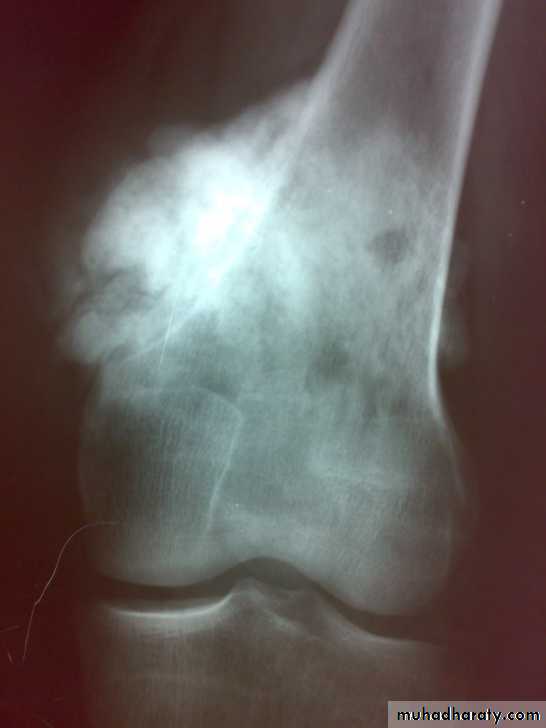

: X-ray are very variable but it show combination of bone destruction and bone formation.

The metaphysis show osteolytic and osteoblastic areas, the cortex is usually perforated and soft tissue shadow may be seen.

There is new bone formation in form of Codman's triangle at periphery of when cortex penetration cause periostium elevation and vertical streaks of calcification in the adjacent soft tissues called sunray appearance.